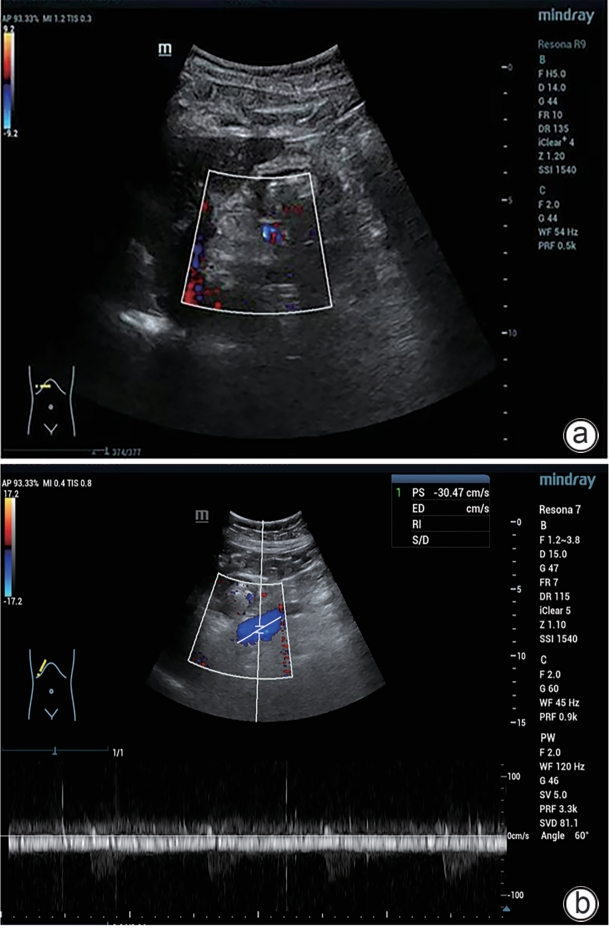

巨大自发性脾肾分流道栓塞联合抗凝治疗门静脉血栓1例报告

黄菊, 王小泽, 罗薛峰, 杨丽

2025, 41(8): 1639-1642. DOI: 10.12449/JCH250825

摘要(508) HTML (175) PDF (3328KB)(68)

摘要:

门静脉血栓是肝硬化患者常见且严重的并发症,门静脉血流动力学的改变与门静脉血栓的发生密切相关。合并巨大的自发性脾肾分流时门静脉灌注减少、血流速度减慢,极有可能削弱门静脉血栓的抗凝效果。本文将报道1例通过栓塞自发性脾肾分流道联合抗凝治疗策略,实现了门静脉的完全再通,然而,仍需高质量的临床研究进一步验证和支持这一策略的有效性。